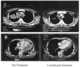

Large cell lung cancer

Large-cell carcinoma (LCC) is a heterogeneous group of undifferentiated malignant neoplasms that lack the cytologic and architectural features of small cell carcinoma and glandular or squamous differentiation. LCC is categorized as a type of NSCLC (non-small-cell lung carcinoma) which originates from epithelial cells of the lung. [Source: Wikipedia ]